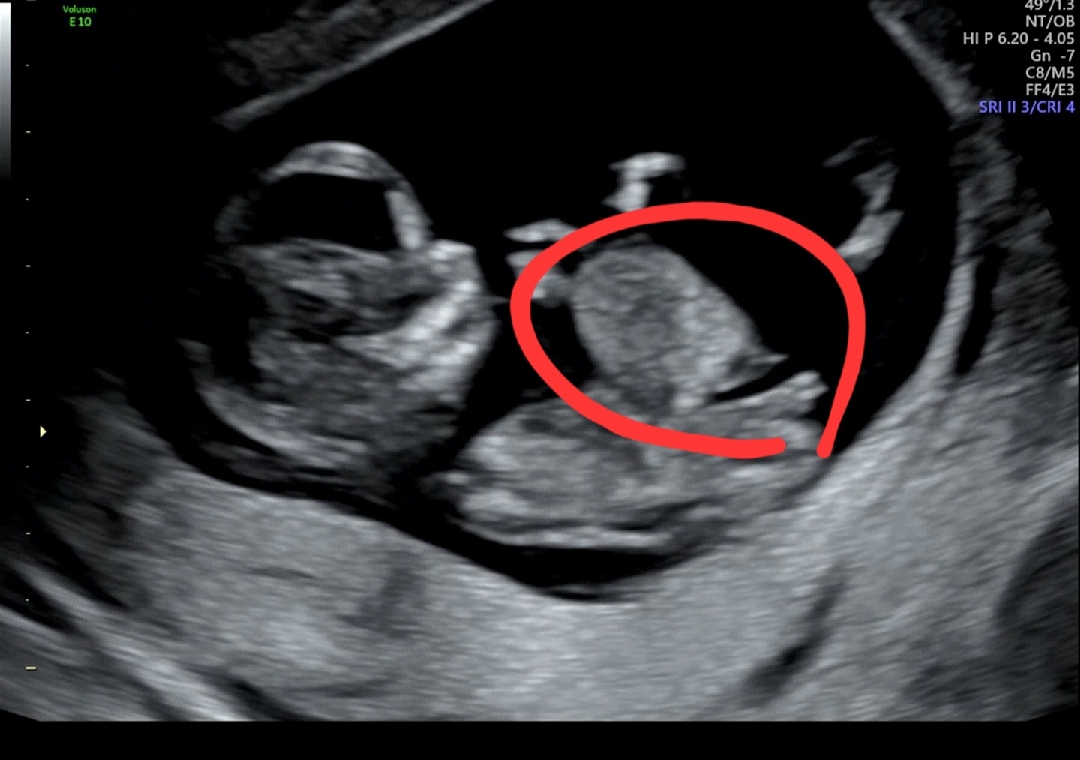

오늘 12주 3일차, 1차 기형아 검사를 하러갔어요 초음파를 보는데 말씀도 없으시고 되게 오래 보시더라고요... 결과는 탈장도 심하고 방광도 모양이 이상하고 뇌단면도 이상하고 결정적으로 목 투명대가 5mm 나왔네요 ... 니프티 검사는 의미가 없다고 하셨고 융모막 검사도 하고싶으면 하셔도 되지만 크게 의미가 없다고 하셨어요.. 다른 의사의 자문을 구하고 싶으면 대학병원으로 의뢰서를 써주겠다 하셨는데 대학병원 진료 알아보니 최소 2주뒤에 예약 된다고 하고... 제가 그냥 놓아줘야 겠죠... 머리로는 다 이해했고 금요일에 중절수술 예약까지 잡았는데 너무 힘드네요.. 1년반 임신준비했었고 한번의 계류 유산 끝에 자연 임신으로 간신히 얻은 아가였는데 12주만에 또 끝이 나네요.. 저도 오늘 웃으면서 각도법 봐주세요 하고 글 남길줄 알았는데 이렇게 될줄은 상상도 못했어요.. 태몽에서 빨간 토마토를 자루에 담았는데 못생긴걸 몇개 더 담아서 그런걸까요.. 도대체 무엇 때문일까 계속 자책하는 밤입니다..... 임신이 참 어렵네요